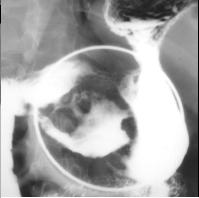

Image en

laculaire eleve intra luminale gastrique a

nultilobulaire ou epassisement de gros plis . S'il y

avait lesion ulceree en association c'est tres

difficile de diagnostic differentielle avec

anenocarcinoma de l'estoma .Image TOGD avec

compressive region antral . |

Meme cas en double de

contrast.TOGD .. |